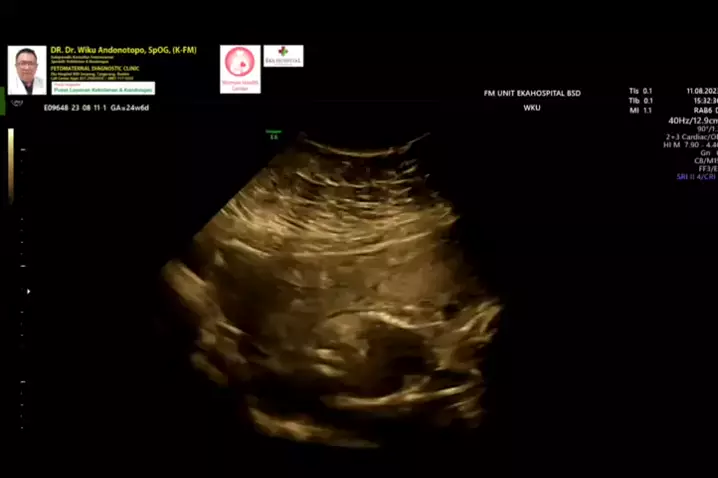

Anhidramnios 24 minggu... #anhidramnios #airketubansedikit #polikandunganekahospitalbsd #spog #fetomaternal #ekahospitalbsd #usgfetomaternalbsd #usgfetomaternaltangerang #fetomaternalsemarang #konsultanfetomaternalsemarang #fetomaternalpontianak #konsultanfetomaternalpontianak #drwikuandonotopo